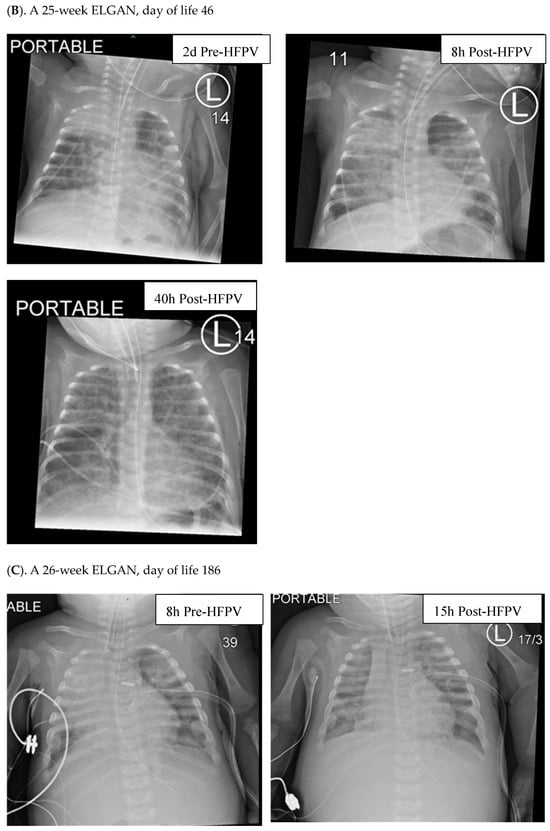

Radiographic improvements were seen in ELGANs, with a representative series shown in Figure 2.

Figure 2.

Radiographs of ELGANs placed on HFPV. Patient (A) is a 25-week gestation infant who was found to have worsening diffuse atelectasis with almost complete opacification of lung fields on a chest X-ray taken 8 h prior to placement on HFPV on DOL 46. Within 6 h after being placed on HFPV, the infant had a dramatic improvement in his clinical status with decreased FiO2 requirements and improved findings on CXR as (shown on the right). Patient (B) is a 25-week gestation infant changed to HFPV on DOL 46. CXRs performed 2 days prior, and 8 and 40 h post-placement on HFPV revealed a more gradual clearing of opacified lung fields. Patient (C) is a 26-week gestation infant with shifting areas of atelectasis, who was changed to HFPV on d186 (left). CXRs 8 h prior to placement on HFPV and 15 h following HFPV, respectively, revealed shifting and then improved aeration.